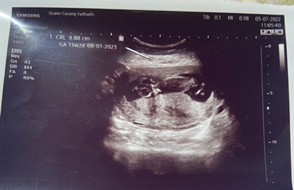

บ้านนี้ 20/1/66 ตอนซาวอายุครรภ์ 11w 4d แต่ใบซาวได้ 13w 2d เครื่องน่าจะวัดจากขนาดของน้องค่ะ แพ้หนักเหมือนกันค่ะ น้ำหนักหายไป4กิโล

บ้านนี้กำหนด 10 มกราคม 2566ค่ะ ยังไม่ทราบเพศน้องเลย รูปซาวด์ตอน10wค่ะ อาการแพ้ดีขึ้นแล้ว แต่แม่สิวเห่อหนักมากกกค่ะ